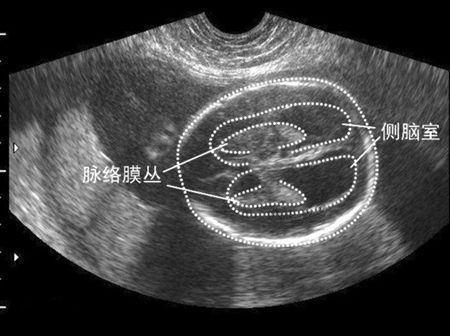

侧脑室增宽,也称脑积水,指的是脑脊液过多积聚于脑室系统中,侧脑室系统扩张,压力升高,超声检查时表现为脑室增宽。一般侧脑室三角区增宽达1.5厘米认为脑室扩大,且越宽程度越重。如果三角区宽1.2~1.4厘米,脉络丛占满脑室内大于50%时,一般认为正常。如脉络丛缩小并呈悬挂状态时,则认为有脑积水存在。